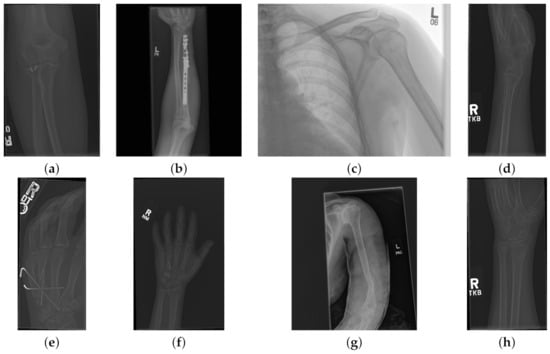

The data used to compare the 11 CNNs was obtained from the public dataset MUsculoskeletal RAdiographs (MURA) from a competition organised by researchers from Stanford University [59]. The dataset has been manually labelled by board-certified radiologists between 2001 and 2012. The studies (n = 14,656) are divided into training (n = 13,457), and validation (n = 1199). Furthermore, the studies have been allocated in groups called abnormal (i.e., those radiographs that contained fractured bones, foreign bodies such as implants, wires or screws, etc.) ( n = 5715 ) or normal ( n = 8941 ). Representative normal cases are illustrated in Figure 1 and abnormal cases in Figure 2. The distribution per anatomical region is shown in Table 1. In this paper, the subset of the wrists was selected. The cases of normal and abnormal wrist radiographs is presented in Table 2. Notice that these were subdivided into four studies.

Figure 2. Eight examples of radiographs with abnormalities (considered positive) of the Musculoskeletal Radiographs (MURA) dataset [59]. (a) Elbow, (b) Forearm, (c) Shoulder, (d) Wrist (lateral view), (d) Lateral view of Wrist, (e) Finger, (f) Hand, (g) Humerus, (h) Wrist. As for the cases without abnormalities, it should be noted the variability of the images and in addition the abnormalities themselves. There are cases of metallic implants some of which are smaller (a) than others (b), as well as fractures.